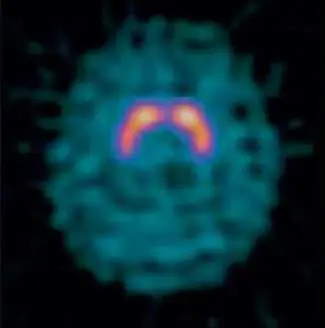

附圖為腦部軸位(axial)SPECT 影像,可見以下特徵:

- 影像中央:雙側對稱性的亮橘紅色高攝取區域,呈「逗號型(comma-shaped)」或「馬蹄型(horseshoe-shaped)」分布,代表雙側**紋狀體(striatum)**的高度放射性藥物聚集。

- 影像背景:周圍大腦皮質呈現均勻低至中度的藍綠色(青色)攝取,代表非特異性背景活性。

- 分布特徵:高攝取集中於紋狀體(包含尾狀核 caudate nucleus 與殼核 putamen),與腦皮質活性形成鮮明對比,整體呈現典型的基底核局部高聚集影像。

此影像的攝取模式(紋狀體/背景活性比值高,非瀰漫性腦血流分布)與腦血流灌注劑(Tc-ECD、I-IMP)的表現截然不同,符合多巴胺轉運蛋白(dopamine transporter, DAT)造影劑的正常影像表現。